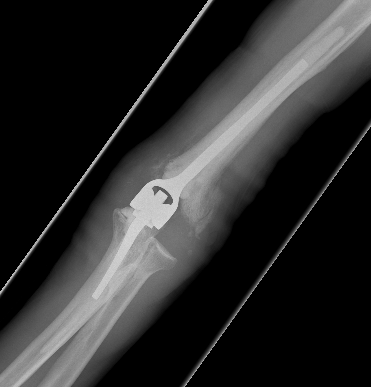

Arthroplasty

Indications

Elderly

Comminuted, osteoporotic distal humerus fracture

Results

Total Elbow Arthroplasty versus ORIF

- RCT 42 patients > 65 years of age

- ORIF verus semiconstrained TEA

- 5 ORIF patients converted to TEA intraoperatively

- better elbow score at 2 years

- no difference in DASH score at 2 years

- mean ROM 107 TEA and 95 ORIF

- systematic review of ORIF v TEA

- better flexion / extension arc and lower reoperation with TEA

- no difference outcome measures

Total Elbow Arthroplasty versus Elbow Hemiarthroplasty

Indications hemiarthroplasty

- younger patient < 65 with unreconstructable fracture

- intact collaterals

Advantages

- able to lift heavier weight

Disadvantage

- instability

- late wear of olecranon cartilage

- RCT of 40 patients > 60 years of age

- hemiarthroplasty versus TEA

- no difference in outcome at 2 years